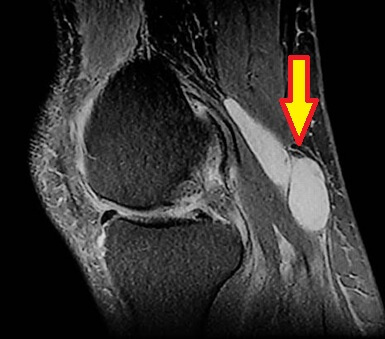

If there is any doubt the doctor can confirm the diagnosis of a Bakers Knee Cyst by performing an ultrasound or MRI scan.

A Bakers Cyst is the most common cause of swelling, pain and stiffness behind the knee.

In some cases however, the popliteal cyst can get quite large, resulting in pain behind the knee, tightness and stiffness, especially when you bend and straighten the knee. A Bakers cyst is the most common cause of swelling behind the knee.